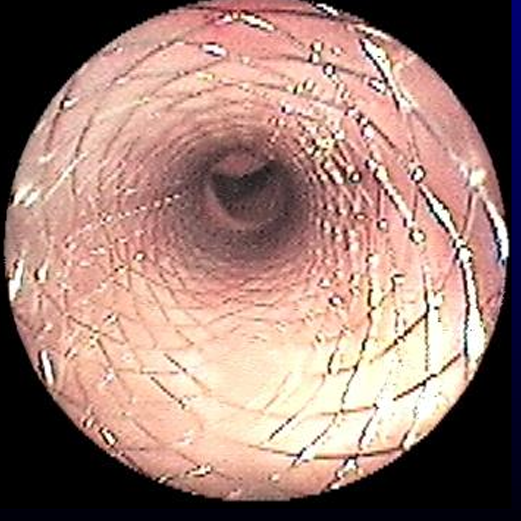

| Radiography | Tracheoscopy |

![]() | ![]() |